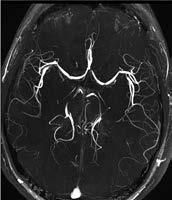

Darstellung hirnversorgender Gefäße

Extrakraniell: Das Verfahren der ersten Wahl ist sicher die FKDS (Abb. 1a–c). Als weitere Verfahren kommen dann die MRA (Abb. 2a, b) und gelegentlich auch die CTA zum Einsatz.

Intrakraniell: Die intrakranielle Gefäßdarstellung ist ein wichtiges diagnostisches Tool in der Therapieplanung und der Behandlung von Gefäßverschlüssen oder Gefäßmissbildungen (Aneurysmen, Angiome). Aktuell stützt sich die Bewertung von intrakraniellen atherosklerotisch-arteriellen Stenosen auf Luminalmessungen mithilfe von DSA, CTA und MRA. Gelegentlich kommt auch der transkranielle Ultraschall (TCD) zum Einsatz. Hierbei stellt die DSA weiterhin den Goldstandard dar. Die MRA wird aufgrund ihrer geringeren Invasivität jedoch wesentlich häufiger eingesetzt. Dabei ist die Timeof-Flight-MRA (TOF-MRA) die am häufigsten verwendete MRATechnik (Abb. 3a), insbesondere zum Ausschluss von Aneurysmen. Bei der intrakraniellen Stenosediagnostik mittels MRA kann infolge von Dephasierungsartefakten der Stenosegrad fälschlicherweise zu hoch eingeschätzt werden. Wegen dieser Einschränkungen hat die TOF-MRA als primäre neurovaskuläre Bildgebungsmodalität an Bedeutung verloren. Außerdem ist ihre räumliche Auflösung im Vergleich zu den anderen MRA-Techniken geringer, sodass die CTA bei der Beurteilung kleinerer Arterienabschnitte der TOF-MRA überlegen ist (Abb. 3b).

Zwar ist der Patient bei der CTA ionisierender Strahlung ausgesetzt und muss sich zudem einer intravenösen Kontrastmittelapplikation unterziehen, jedoch definiert die CTA die anatomische Konfiguration und die Beziehung der Pathologie zur Umgebung besser. Verschiedene Studien in

Abb. 3a

Abb. 3b

Abbildung 3a, b: Intrakranielle Gefäßdarstellung.

a: Mittels Time-of-Flight-MRA (TOF-MRA) erhobener Normalbefund (Arterien sind hell dargestellt).

b: In der CT-Angiographie zeigt sich ein Verschluss der A. cerebri media rechts.

der Vergangenheit haben jedoch gezeigt, dass es keinen signifikanten Unterschied hinsichtlich der

Genauigkeit der Gefäßdarstellung zwischen CTA und MTA gibt (Literatur beim Verfasser).